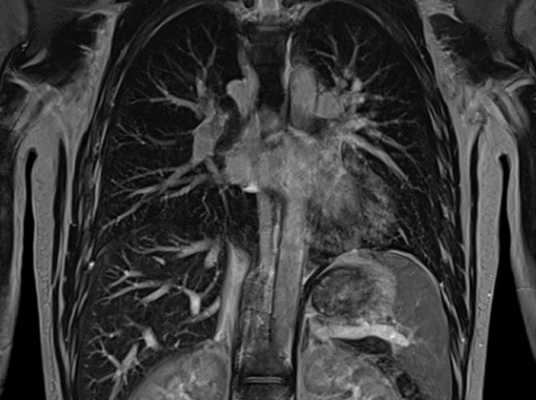

Мультиспиральная КТ грудной клетки, 3D-реконструкция

Специалисты выделяют в средостении три области: центральное (сосудистое пространство с перикардом и его содержимым, сосудами и лимфатическими узлами), переднее (жировая клетчатка, вилочковая железа, внутренние грудные артерии и лимфоидные ткани) и заднее (трахея, пищевод, нисходящая часть грудной аорты, лимфоузлы и паравертебральные пространства грудной клетки). Соответственно, все патологические процессы, которые протекают в данных зонах, могут быть видны.